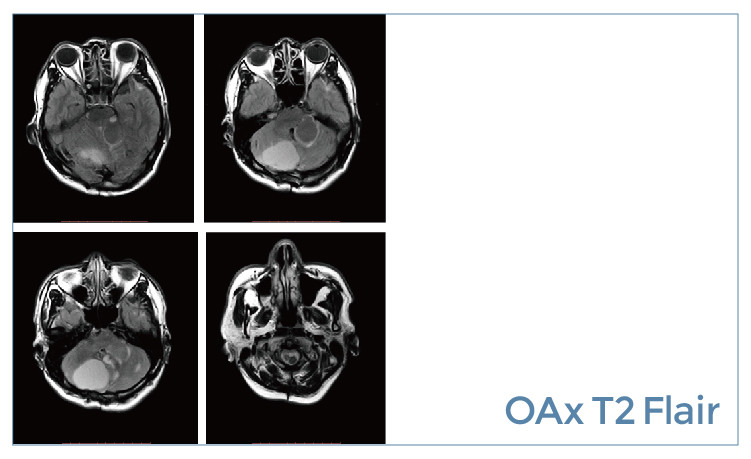

【朗润影像档案】磁共振影像病例分享(编号20190614)